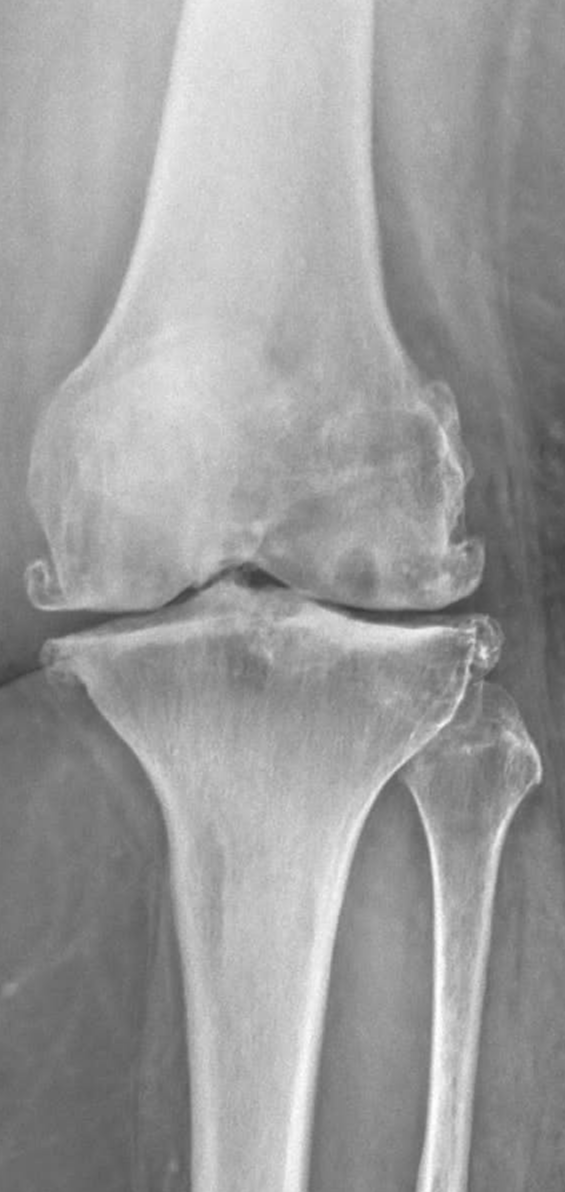

Vous recevez la radiographie de Mme M, 86 ans.

Elle n’a aucun antécédent médicochirurgical, aucun traitement et était jusqu’à présent en très bon état général. Elle a un IMC à 24kg/m².

Vous lui aviez prescrit cette radiographie devant une gonalgie gauche chronique d’horaire mécanique (depuis plus de 2 ans), qui la limite dans ses activités quotidiennes.